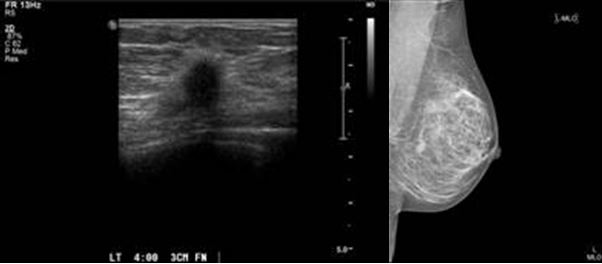

Hạch vú lành, nhỏ có, lớn có ở một bên hay bên vú. Chúng nằm trong vú, hay chạy, nên gọi là ‘bướu chuột’ (breast mouse). Chúng được nhận diện bởi chụp hình vú (mammogram) hay siêu âm. Nếu nó kết hợp bằng tế bào liên kết thì gọi là sợi fibrosis, còn bằng ống và túi li ti thì gọi là adenoma. Nếu cả hai thì gọi là fibroadenoma.

1. Quang tuyến vú (mammography).

- Chụp hình vú có thể phát hiện được ung thư 2 năm trước khi tay sờ được cục bướu nhỏ.

- Chụp hình vú cũng có thể phát hiện các bướu ở bịnh nhân phì mập, mà tay không phát hiện được

- Tuy nhiên cũng có thể sai, cần xác định lại bằng phương pháp khác.

2. Siêu âm vú.

Siêu âm có cái lợi trong trường họp nghi ngờ. Siêu âm phát hiện các túi hay hơn chụp hình vú. Nhớ khi siêu âm ngực, không nên tắm bằng xà bông thơm, thoa dầu thơm,có thể làm hình sẽ mờ tưởng là bị bịnh?

Rút nước ở núm vú chảy ra đem đi thí nghiệm. Có thể lấy kim đâm (fine needle biopsy FNB) vô túi nước (cyst) hay bướu, rút nước hay tế bào ra rồi xét nghiệm.